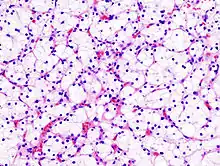

![]() يتكون النوع الأول من سرطان الخلايا الكلوية الحليمية من حليمات مغطاة بطبقة واحدة أو طبقتين من خلايا مكعبة صغيرة مع قليل من السيتوبلازم، ويتكون النوع الثاني من حليمات مغطاة بخلايا يوزينية كبيرة مرتبة بطريقة غير منتظمة. |

10–15% |

|